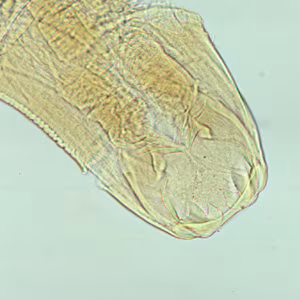

Adult hookworms.

Adult hookworms reside in the small intestine of their hosts. A. duodenale males measure approximately 8—12 mm long, and females measure approximately 10—15 mm long. N. americanus males are 5—9 mm long, females 9—11 mm. Males are bursate, with two spicules that are fused at the distal end in Necator spp. but not in Ancylostoma spp. Adults of both sexes have a buccal capsule containing sharp teeth (Ancylostoma) or cutting plates (Necator).